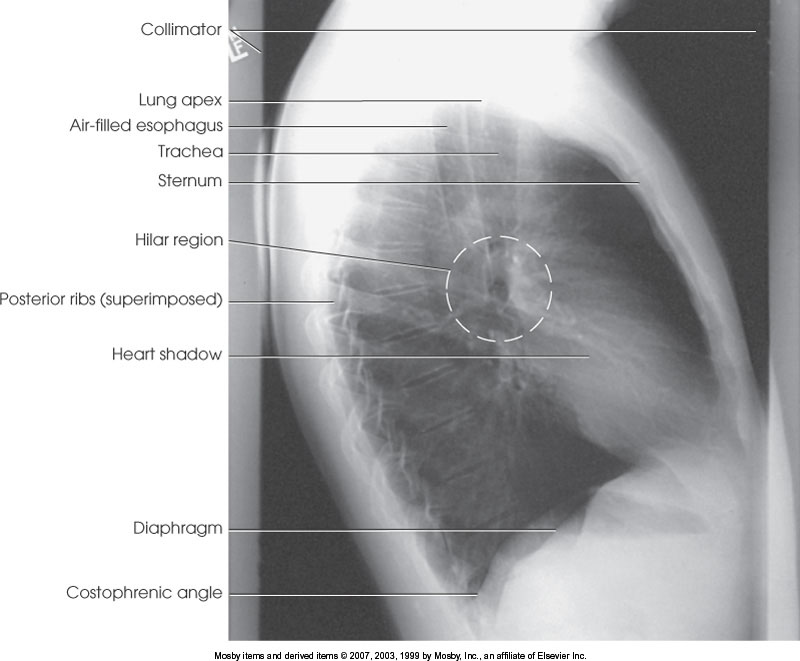

What position is demonstrated?

Lateral Chest